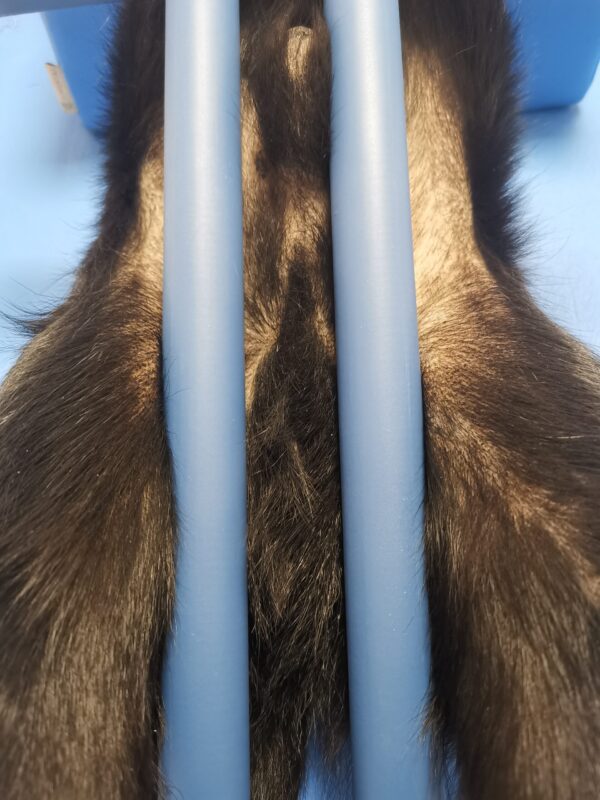

Narzędzie wspomagające ocenę luźności stawów biodrowych podczas badania ortopedycznego. Dystraktor wykorzystywany jest podczas diagnostyki dysplazji stawów biodrowych.

Urządzenie jest regulowane, w pełni kompatybilne z większością psich i kocich pacjentów. Regulacja rozstawu wałków od 6,5 do 28 cm.